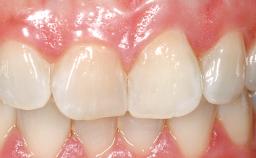

Immediate Flapless Placement of an Implant in a Maxillary Left Central Incisor Site

A 42-year-old female patient was referred to our clinic at the School of Dentistry of the University of São Paulo in November 2004, presenting a deficient restoration in the upper left central incisor. The clinical examination revealed no gingival retraction or any signs of gingival inflammation and, therefore, previous periodontal treatment was not considered. The patient presented a high lip line at full smile and a thin tissue biotype. This combination characterized a high-risk situation from an anatomic point of view, which required careful preoperative planning and cautious surgical execution.

Lip Line No exposure of papillae Exposure of papillae Full exposure of mucosa margin

Periodontal Phenotype Low-scalloped, thick Medium-scalloped, medium-thick High-scalloped, thin

Soft Tissue Contour and Volume Ideal